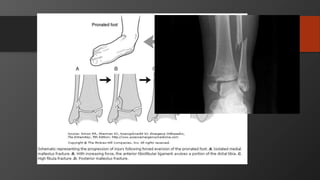

Fifth Metatarsal Fractures

• Common injury

• Divided into 3 zones

• Zone 2 is Jones fracture

• Zone 1 is Pseudojones fracture

Lisfranc Injury